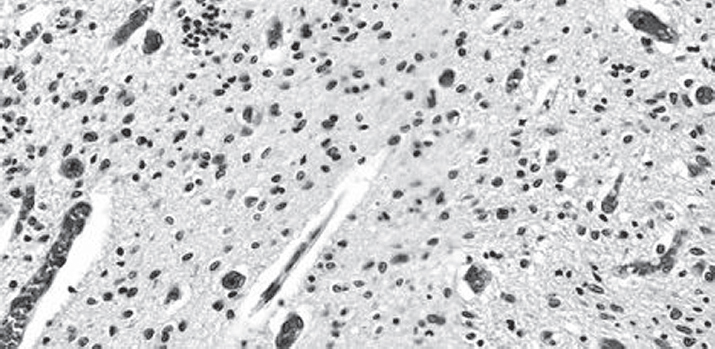

Научные работы последних лет, направленные на изучение патогенеза ВЖК, свидетельствуют, что у детей, родившихся в 37 нед. гестации и позже, ВЖК возникают чаще вследствие повреждения сосудистого сплетения, а не из герминативного матрикса, который редуцируется к периоду доношенности [2]. В нашем случае следует обратить внимание на кровоизлияние из сосудистого русла редуцирующегося герминативного матрикса в субэпендимальную область с распространением в собственно вещество головного мозга и далее с выходом крови непосредственно в полости боковых желудочков (рис. 3).

Рис. 3. Нарушение целостности эпендимы, с кровоизлиянием и выходом в полость желудочков. Окраска гематоксилином и эозином. Ув. ×10 / Fig. 3. An ependymal lesion with an intraventricular hemorrhage (H&E stain). Magnification ×10